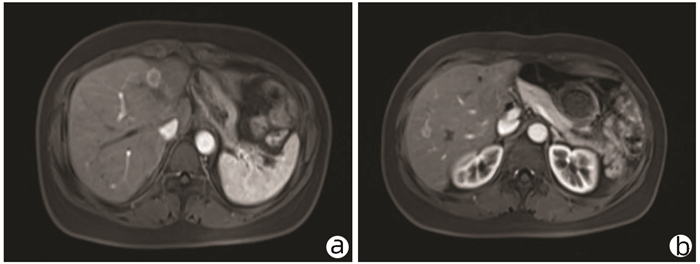

Endoscopic treatment of gastroesophageal varices complicated by posterior reversible encephalopathy syndrome: A case report

Tingting YU, Shanshan JIANG, Mengran ZHU, Yun BAI

2022, 38(1): 177-179. DOI: 10.3969/j.issn.1001-5256.2022.01.030

Abstract(830) HTML (198) PDF (3069KB)(60)

Abstract: